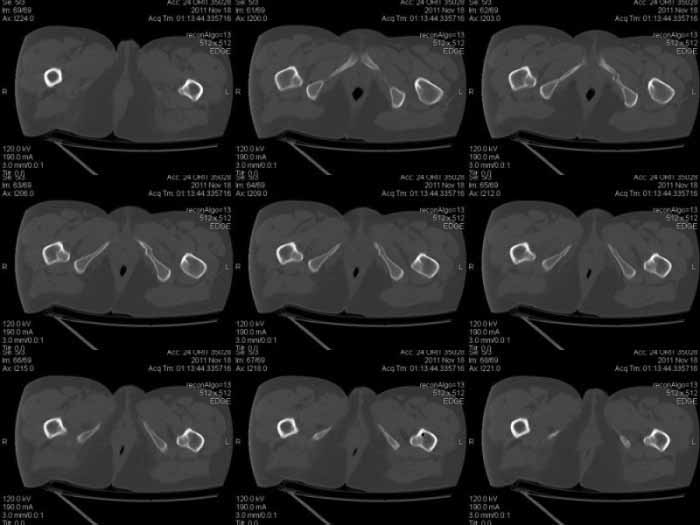

Кт снимки

КТ срезы помогают увидеть мелкие фрагменты и маргинальную импакцию, но на ваших мелких срезах трудно увидеть повреждение боковой массы крестца? Классифицировать перелом вертлужной впадины по Летурнелю все таки привычнее на косых Judet снимках.

Некоторые переломы вертлужной впадины между собой трудно отличаются, и надо проводить дифференциальную диагностику переломов: Т-образного, двух колонного и комбинации поперечного с переломом задней стенки (Associate

Transverse &Posterior Wall). Отсутствие вовлечения крыла подвздошной кости при двухколонном и наличие перелома в седалищной кости говорит о

Т-образном переломе.